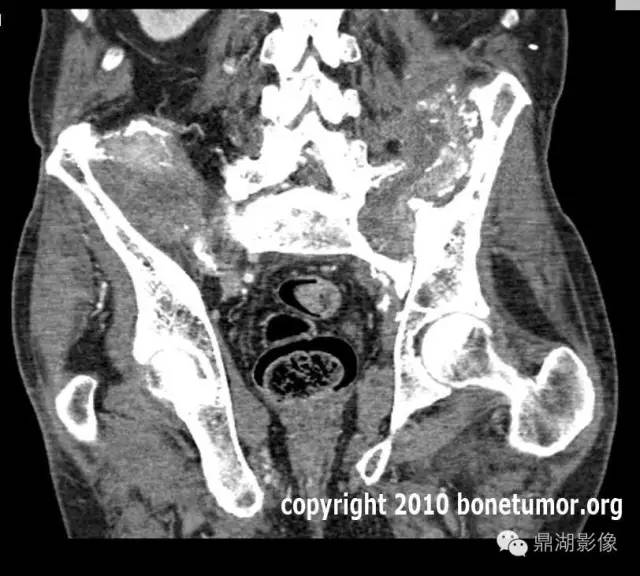

肾细胞癌骨转移

(六)肾癌骨转移 约23.5%发生骨转移,多见于股骨、肱骨、脊柱、骨盆、肋骨等处。常为单发,溶骨性破坏,骨干稍有膨胀,可侵蚀破坏骨皮质,发生病理性骨折。骨缺损区内有骨性间隔出现,颇似原发性肾肿瘤。也可为硬化型,或有广泛多层骨膜反应。